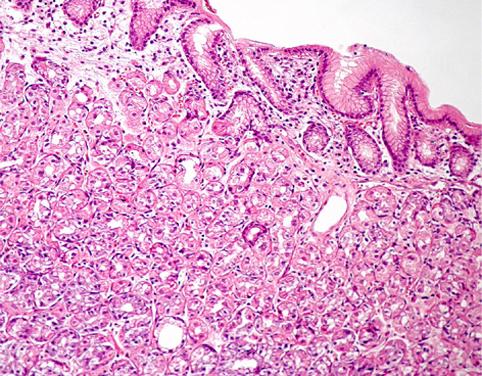

질환(병리주체)의 분류 종양양 병변/이소성 점막

부위(장기별) 십이지장/구부

검사방법 마이크로

종양의 최대경(밀리미터) 1~9